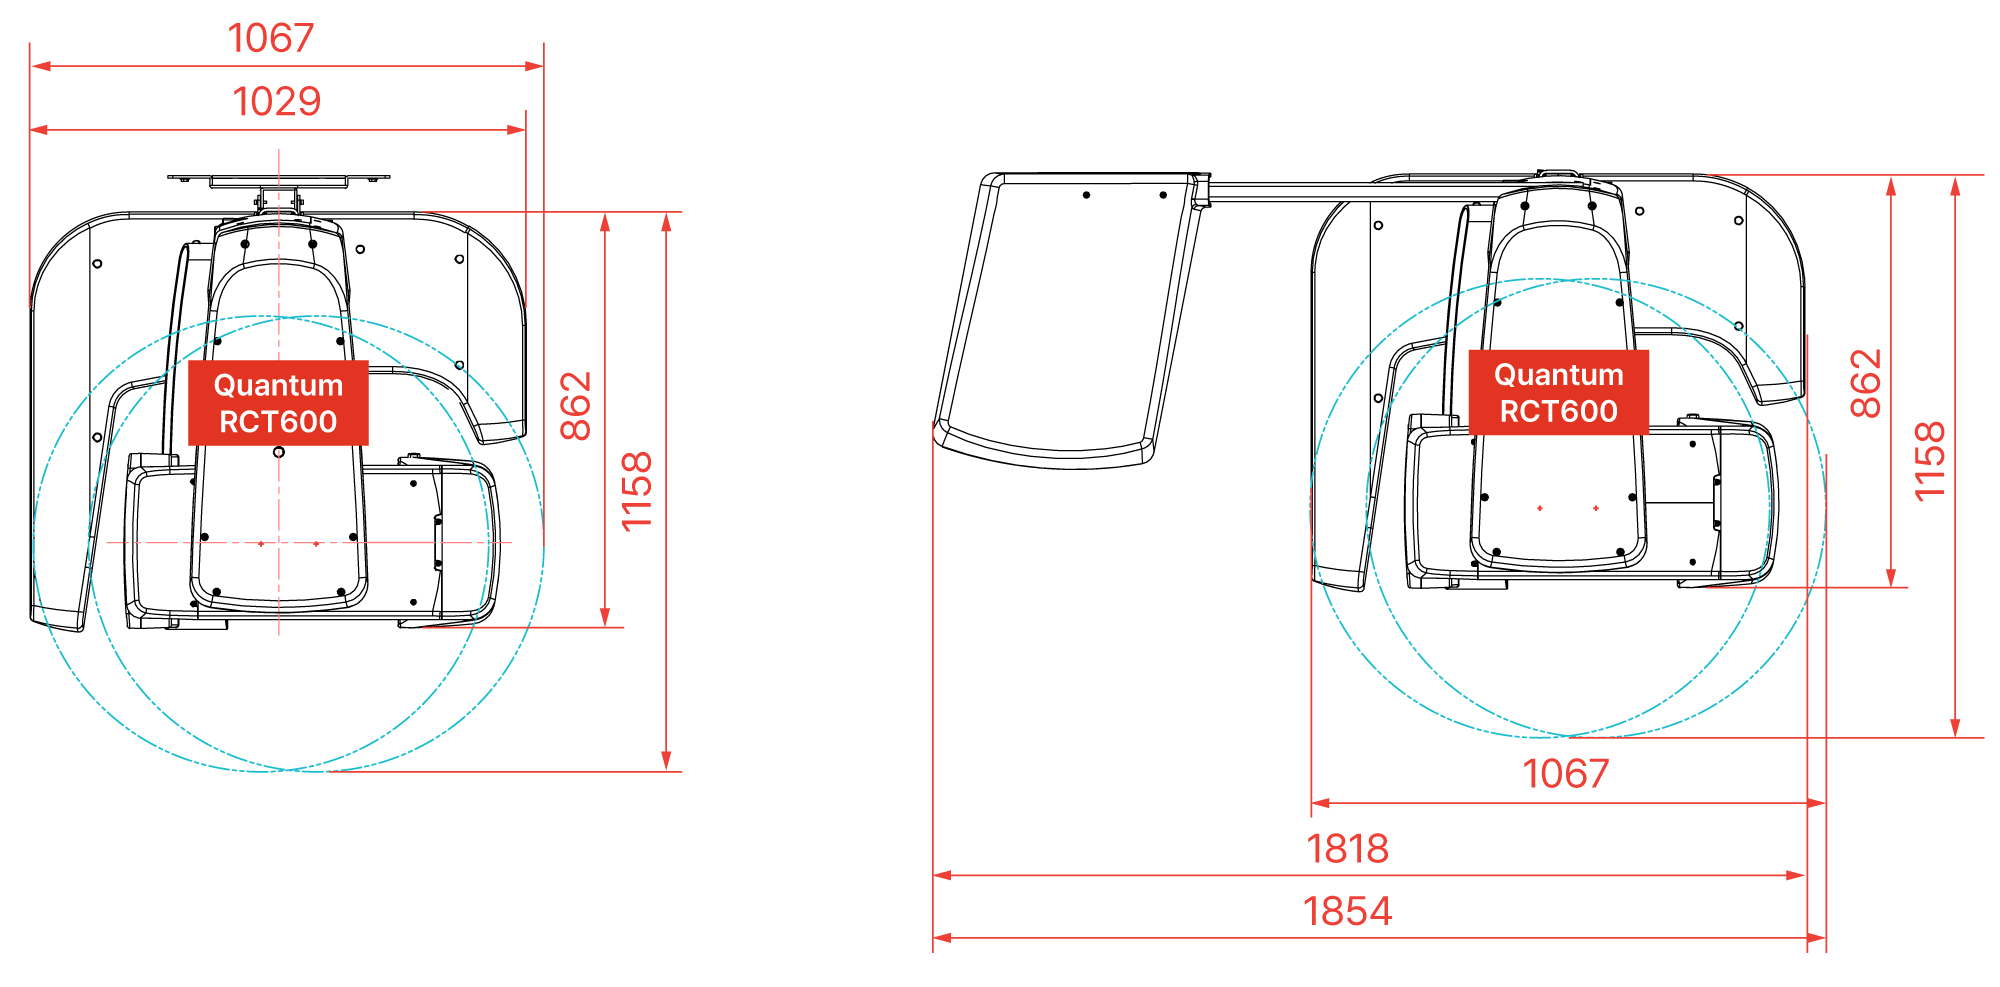

DIMENSIONS (RAY Quantum)

DIMENSIONS (RAY Quantum)